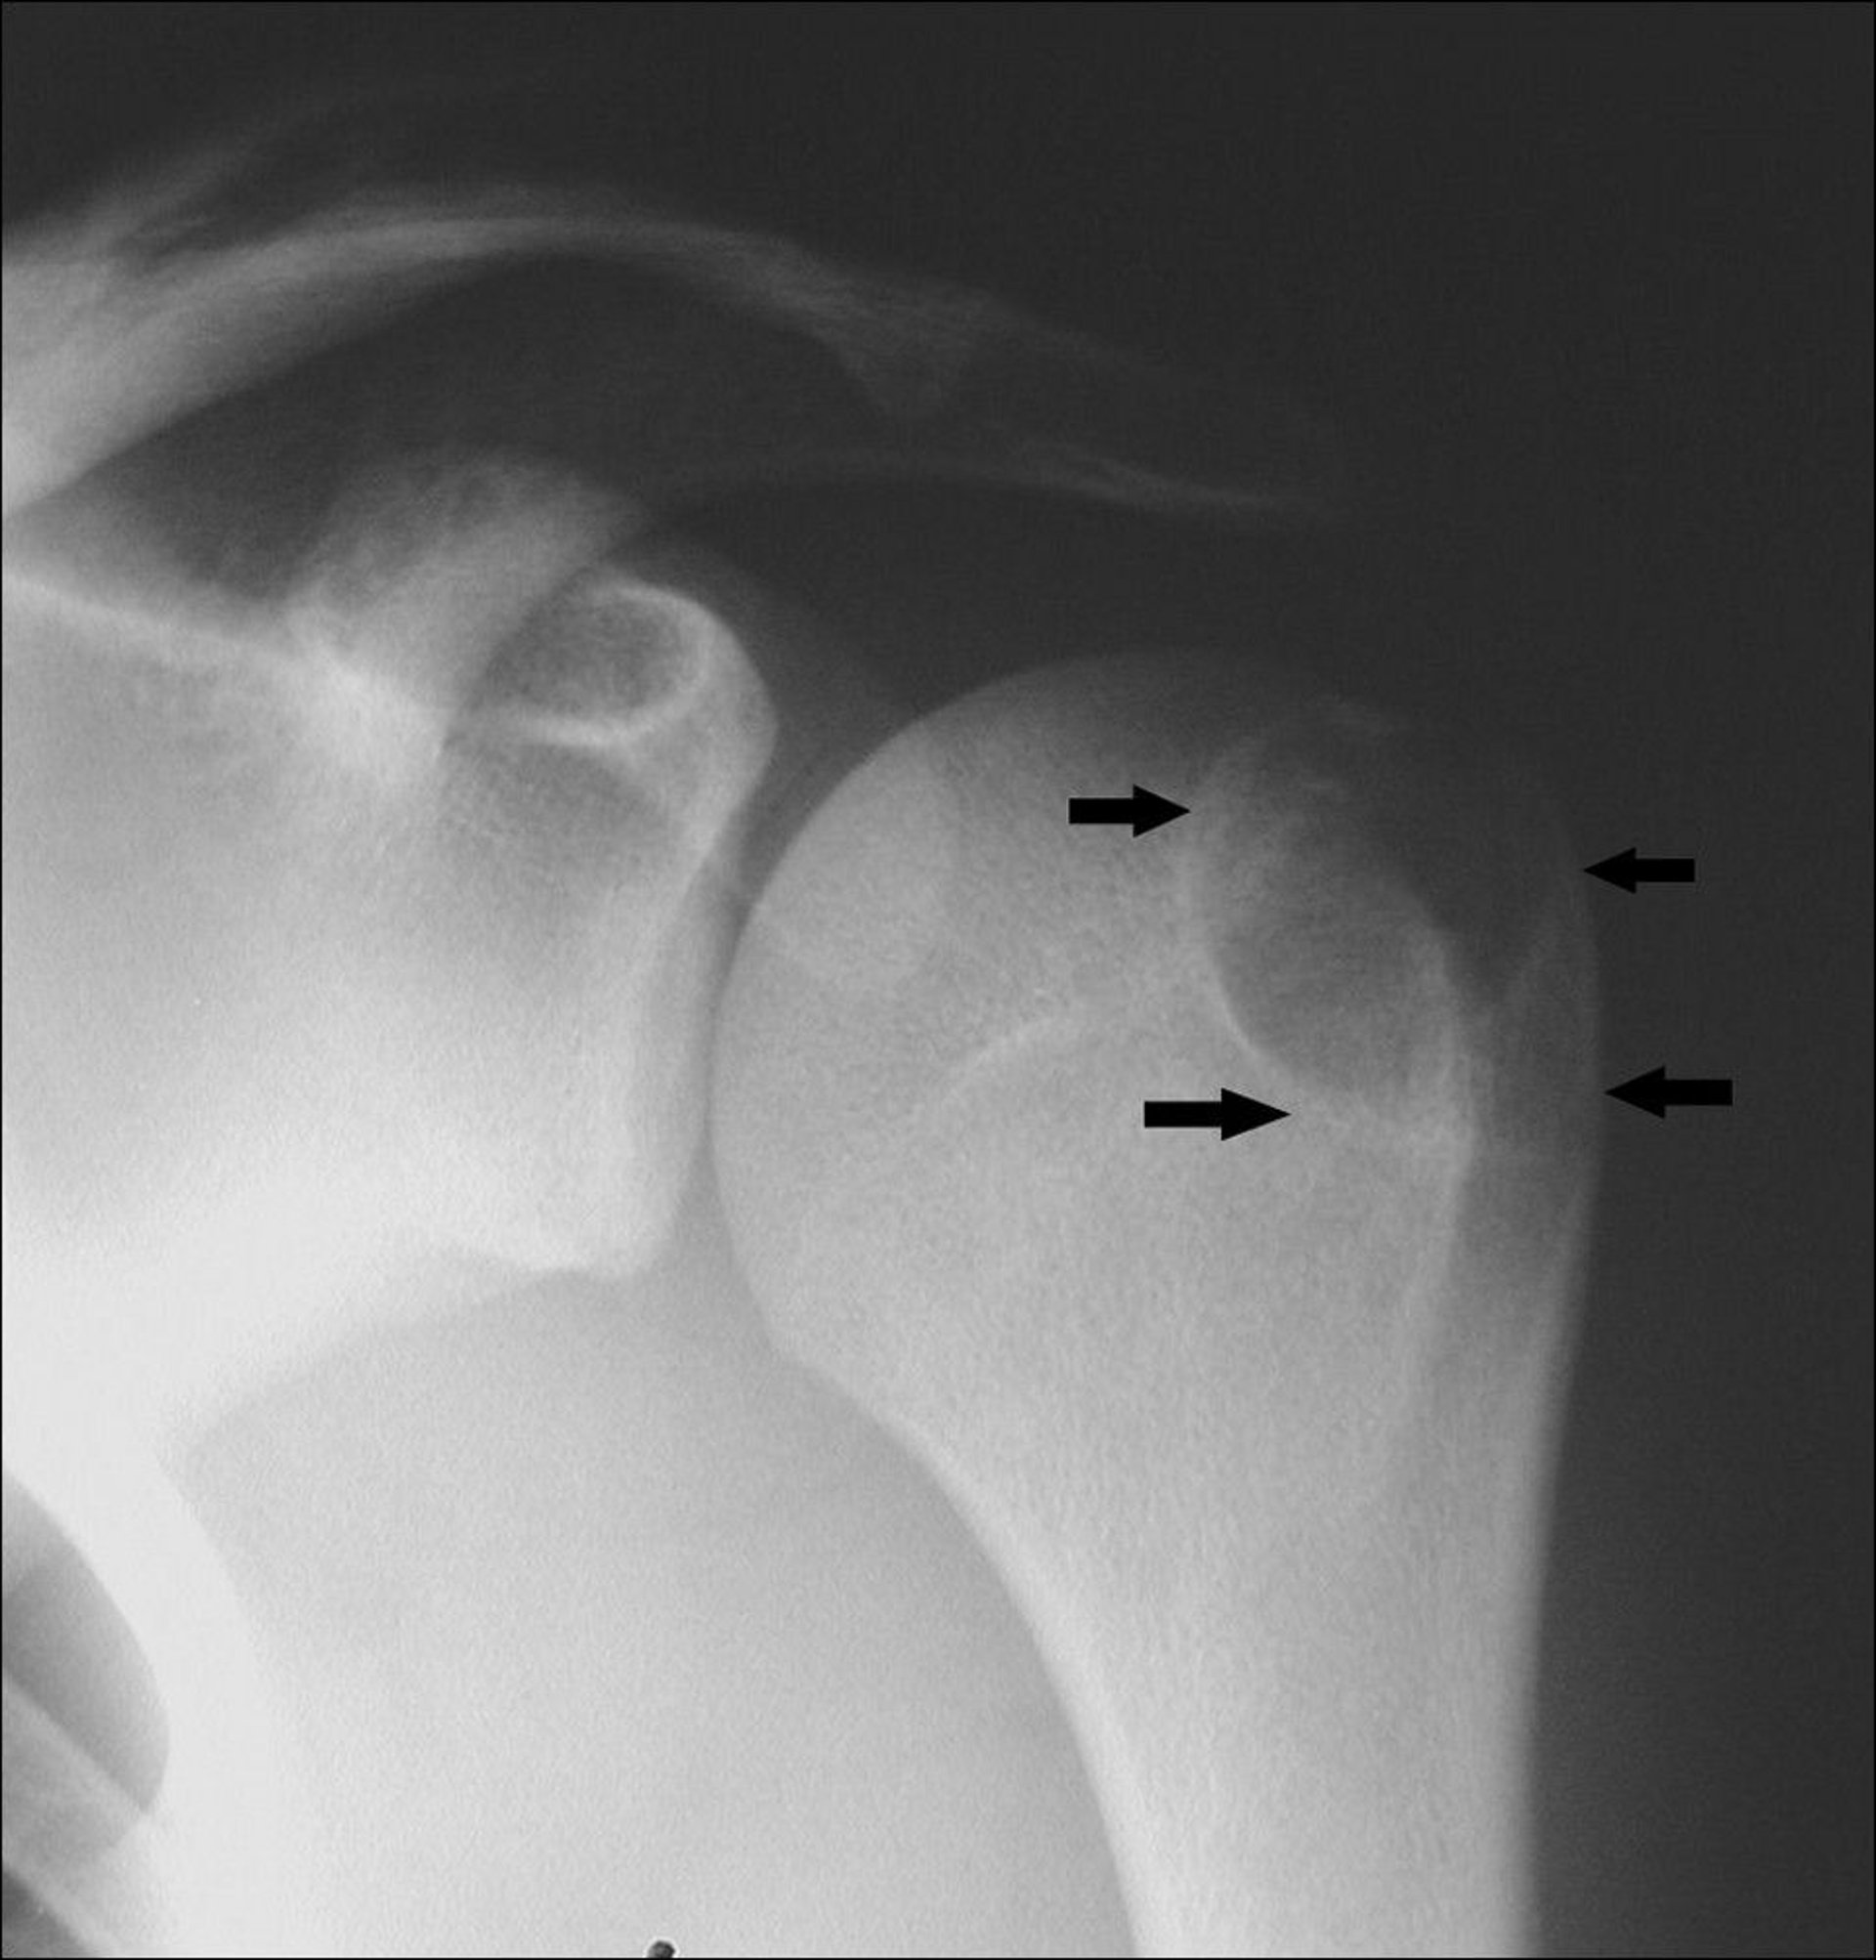

This shoulder radiograph shows a chondroblastoma in the humerus at the greater tuberosity apophysis (arrows).

Image courtesy of Michael J. Joyce, MD, and Hakan Ilaslan, MD.